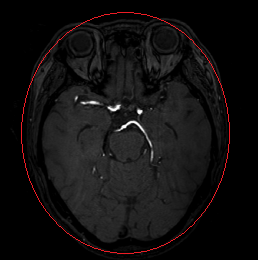

이는 신경외과 수술을 계획하고 수행하는 데 도움이 된다는 필요성이 제기되었습니다. 이때 사용되는 데이터는 자기공명 혈관조영술 (MRA)이라는 기법을 통해 촬용된 데이터이며, MRA 중에서도 3D TOF MRA를 통해 진행됩니다.

논문에서 제안된 임계치 분할 알고리즘을 사용하여 3차원 TOF MRA 영상에서 뇌혈관을 자동으로 추출한 결과입니다.